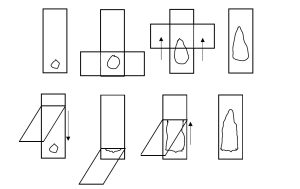

La citología puede ser realizada mediante punción con o sin

aspiración con aguja fina (PAF o PAAF respectivamente), impronta

o raspaje; entre las primeras dos técnicas no hay grandes

diferencias y hay quienes se sienten más cómodos con una u otra,

aunque utilizamos la PAF mucho más a menudo debido a menor

contaminación y ruptura celular por la aspiración. El uso del diámetro y largo de las agujas

pueden ser recomendadas. Los movimientos deben ser en forma de abanico una vez ingresada

en el tumor sin salir del mismo, en ese momento si es con aspiración debe ser realizada (debe

tenerse cautela de no aspirar cuando se sale de la formación).

Una vez que se terminó de realizar la maniobra:

a) Se desacopla la jeringa y se llenara de aire (no es recomendable usar

jeringas de más de 5 ml)

b) Se expulsará el contenido sobre un portaobjetos limpio y seco

c) Se realiza el extendido con presión suave en un solo movimiento

La toma de muestra y su extendido es clave para una correcta interpretación de la